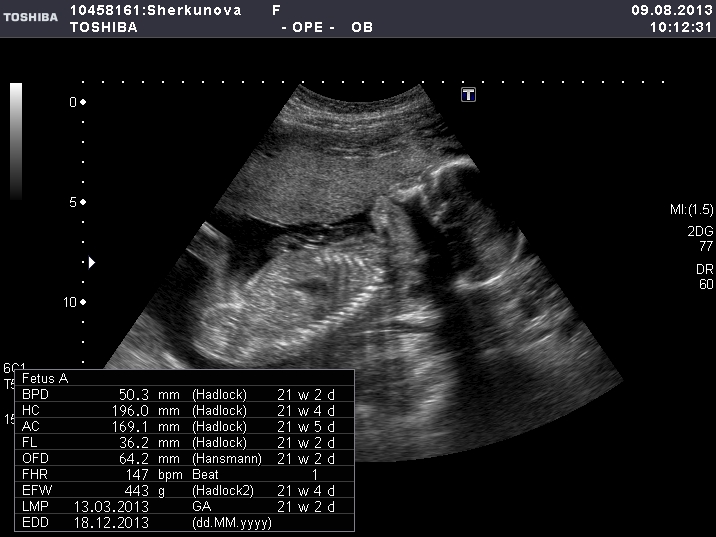

Вопросы про УЗИ, обследования и анализы: что, где, как, когда?Была на УЗИ - у нас всё хорошо (славаБогу), соответствуем сроку, плацента поднялась к норме. И подтвердили девочку!! Я всё-всё рассмотрела, даже пальчики на руках и ногах! И узистка сделала оч полезный снимок - вид сверху на попу, ПИСЮ и согнутые в коленках ножки! Ну я так мотрю ,вроде ж не висит точно ничего лишнего для девочки! Правда ведь?! А то я хочу ну оч девчачью коляску покупать, уже выбрала, так чтоб конфуза не было)))